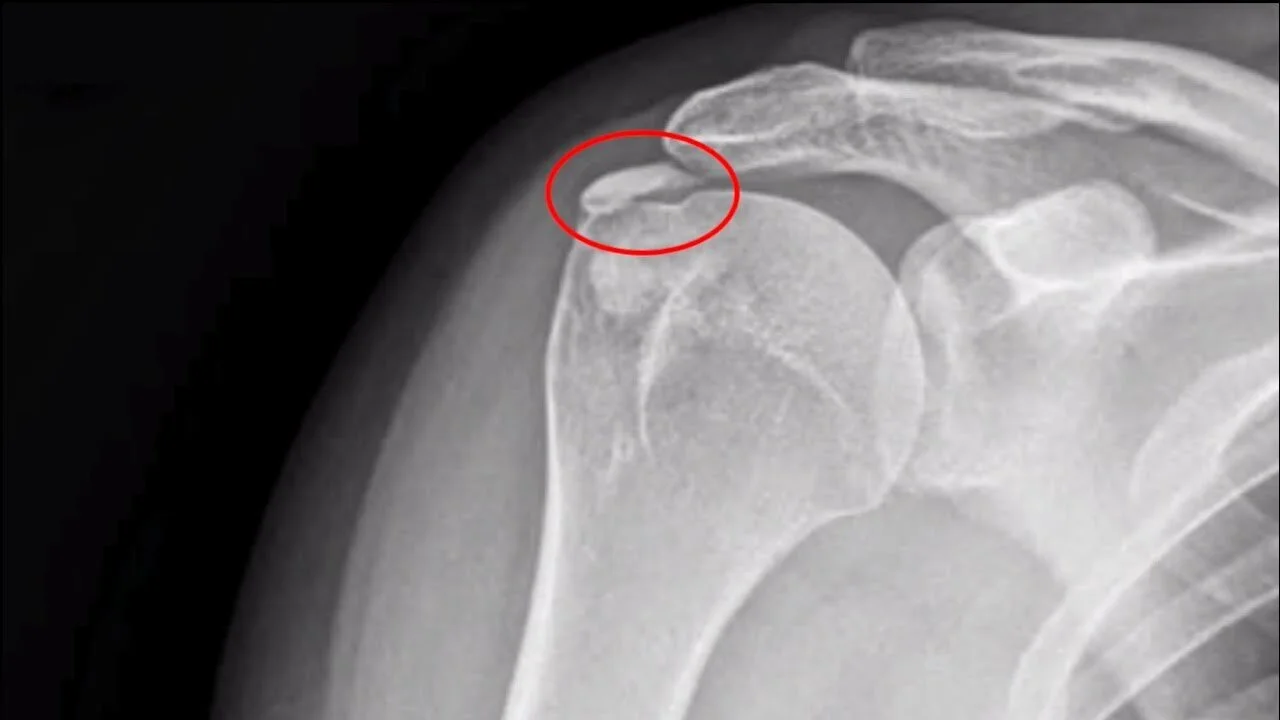

FRATTURE LUSSAZIONI DEL CINGOLO SCAPOLOOMERALE E STERNOCLAVEARE O.T